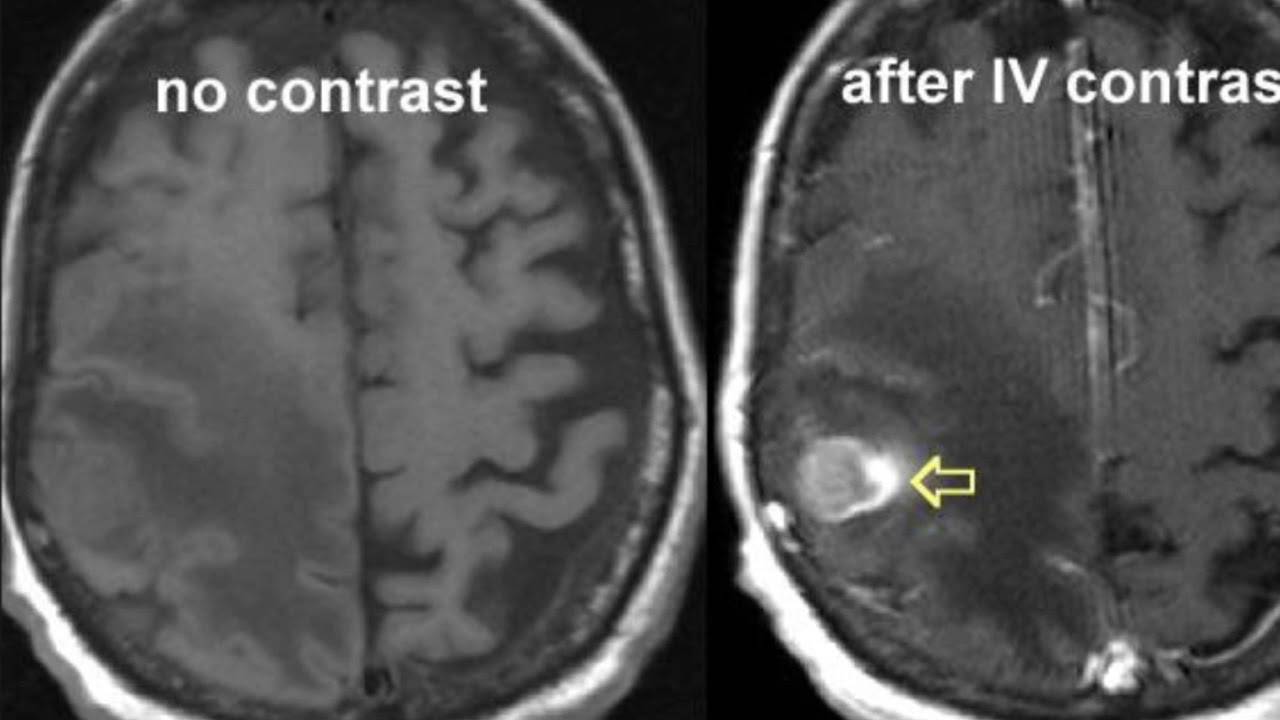

В чём разница между сканированием с контрастом и без? Обычно первая процедура МРТ делается без контраста, если нет особых показаний к этому. Если по результатам исследования у врача остались или появились новые вопросы, то назначается МРТ с контрастированием.

Но в некоторых случая сразу же делается томография с контрастом. Чаще всего это происходит, когда требуется исследовать сосуды пациента. Без контраста они значительно хуже визуализируются на снимках.

На основании этих проекций формируется представление о реальных физических размерах, взаимном месторасположении, структуре и состоянии любого внутреннего органа. По МРТ-снимку можно локализировать опухоль с диаметром от 1 миллиметра, найти внутреннее кровотечение, травматическое изменение в тканях или патологию их развития, очаг воспаления и зону инфекционного поражения. Если во время сканирования в кровь пациента ввести контрастное вещество, проекция виртуального среза станет более отчетливой — диагност наведет «резкость» на снимке, повышая точность прогнозов.

МРТ головного мозга с контрастом обязательно при диагностике онкологических процессов.